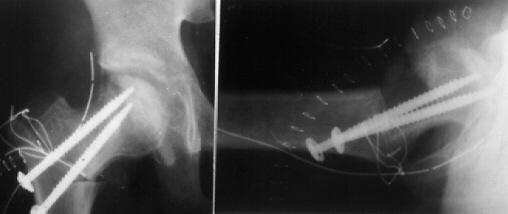

K.B.. 12-year-old boy. B.W. 63 kg(139 Ib.) . Perthes disease.

He had right hip pain and limping for seven weeks. When he was

first seen at University Hospital of Niigata, the right femoral

head was deformed already and collapsed slightly on X-ray.

The lateral part of the femoral head showed an impingement lesion.

Because good sphericity of the posterior part of the femoral head

was still preserved,

Sugioka's rotational osteotomy was advised. Pre-operative range

of motion was flex.90, abd.35, e.r. 40, and i.r. 15. The femoral

head was anteriorly rotated by 75 degrees and varus angulation

by 15 degrees was made.